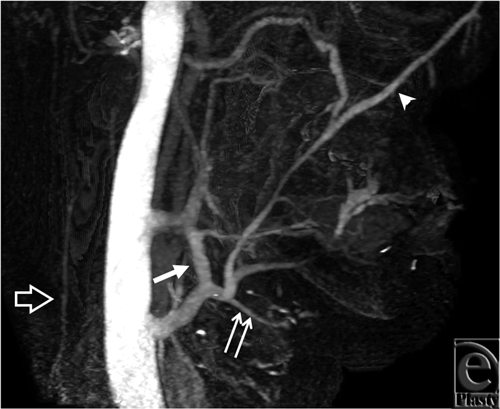

Venous anatomy

For all 3 subjects, cine image analysis was capable of identifying large veins, namely internal and external jugular, anterior jugular, and the major confluences of facial veins (see Movies 1-3) that are relevant to major reconstructive surgery for anastomosis. In injured tissues that demonstrate substantial collateralization, however, webs of collateralized veins appeared as a thin sheet of contrast, making it difficult to identify small veins and their detailed anatomy. In this regard, static images allow more direct viewing of the trajectories of individual vein segments and their precise paths (Figs 3 and 4).